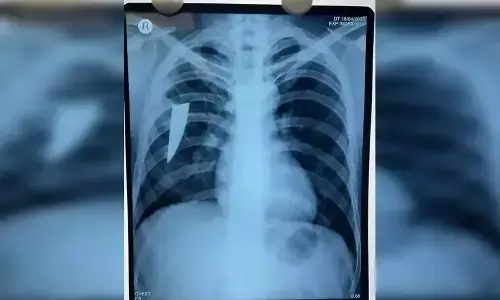

Broken knife removed from man’s lungs in MKCG